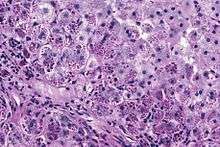

Alpha 1-antitrypsin (A1AT) is produced in the liver, and one of its functions is to protect the lungs from neutrophil elastase, an enzyme that can disrupt connective tissue.[1] Normal blood levels of alpha-1 antitrypsin may vary with analytical method but are typically around 1.0-2.7 g/l.[6] In individuals with PiSS, PiMZ and PiSZ genotypes, blood levels of A1AT are reduced to between 40 and 60% of normal levels. This is usually sufficient to protect the lungs from the effects of elastase in people who do not smoke. However, in individuals with the PiZZ genotype, A1AT levels are less than 15% of normal, and patients are likely to develop panacinar emphysema at a young age; 50% of these patients will develop liver cirrhosis, because the A1AT is not secreted properly and therefore accumulates in the liver . A liver biopsy in such cases will reveal PAS-positive, diastase-resistant granules. Unlike glycogen and other mucins which are diastase sensitive (i.e., diastase treatment disables PAS staining), A1AT deficient hepatocytes will stain with PAS even after diastase treatment - a state thus referred to as diastase resistant.